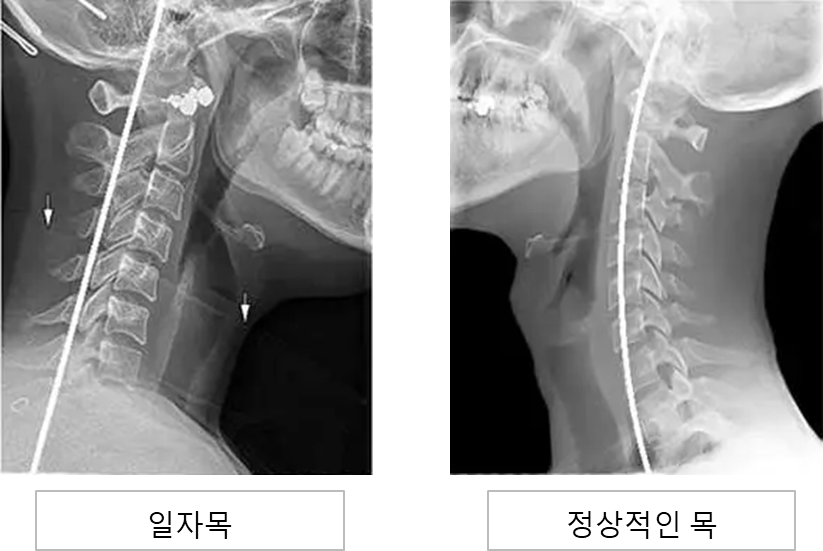

스마트폰을 사용하면서 잘못된 자세가 습관화 되면서 경추뼈가 C자형에서 일자형으로 바뀌게 되는 것을 말한다. 최근 젊은층 사이에서 일자목 환자가 급증한 이유가 바로 스마트폰 사용의 폭발적인 증가이다.

일자목은 보통 목에 C자 곡선이 없고 일자로 곧게 펴져있거나, C자 반대로 꺾였을 경우를 말한다. 일자목의 가장 큰 문제점은 충격을 완화하는 능력이 떨어진다는 것이다. 충격이 생겼을 때 충격을 완화하는 역할을 할 수 없어서 작은 충격에도 척추와 머리에 그대로 전달되어 위험하다.